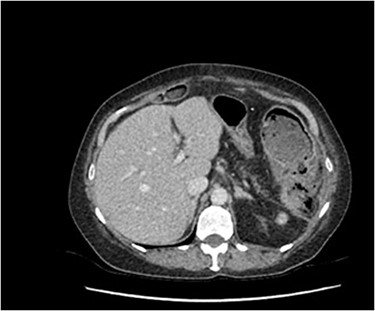

Within 14 hours postoperatively, she developed an erythematous patch on her left thigh, and a creatine kinase of 19 000. A bedside finger test was performed which showed dirty dishwater fluid, necrotic fat and lack of bleeding. She was taken to theatre for urgent debridement for suspected NF. Antibiotics were changed to Meropenem, Vancomycin, Lincomycin and Fluconazole. She had extensive debridement of the soft tissue circumferentially on the left thigh, including some muscle. In 10 hours postdebridement, there was a radiological evidence of disease progression with gas in muscle compartments on the lower limb X-rays (Fig. 2a and b), and CT abdomen and lower limbs demonstrating gas throughout the whole left leg and a non-contiguous area in the right gluteal region (Fig. 3a and b). A diagnosis of multi-focal non-contiguous necrotising myositis was made.

(a) Air in the deep medial and posterior compartments of the thighs and calf suggestive of residual infection in the deep compartment. (b) New finding of air in the right gluteus medius muscle.